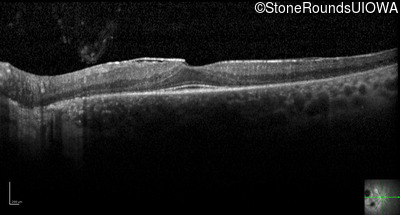

Optical Coherence Tomography - Left - 20/20

Exemplar / OCT Stack

OCT Stack